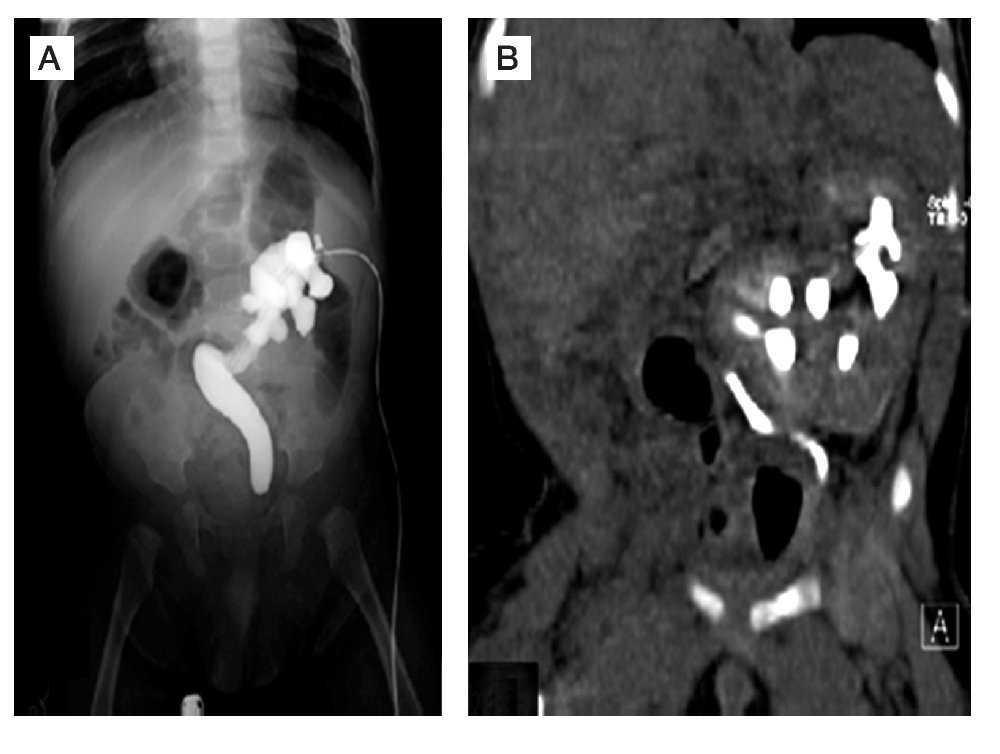

Ante los hallazgos en la tomografía, se decidió realizar una cistoscopía en la cual se observó un meato ureteral izquierdo único, sin ser posible su cateterización para la realización de una pielografía retrógrada, por lo que se procedió a realizar una exploración quirúrgica por lumbotomía y drenaje del urinoma, con colocación de nefrostomía. Se realizó una pielografía anterógrada demostrando la fusión renal y piélica, con presencia de un uréter único asociado a un megauréter obstructivo secundario a la estenosis de la unión ureterovesical (UV) (Figura 3). En un segundo tiempo quirúrgico, se efectuó una remodelación ureteral tipo Hendren con reimplante tipo Politano Leadbetter. El paciente evolucionó satisfactoriamente, se corroboró el paso del medio de contraste hacia la vejiga en una pielografía anterógrada de control (Figura 4). Se retiró la sonda de nefrostomía de manera definitiva, cursando hasta el momento con la función renal conservada.

Figura 3. A) Pielografía anterógrada en la que se observa un sistema colecto único con un megauréter obstructivo secundario a estenosis de la unión ureterovesical. B) Nefrostografía combinada con cortes tomográficos coronales en la que se observa la presencia de nueve grupos caliciales.